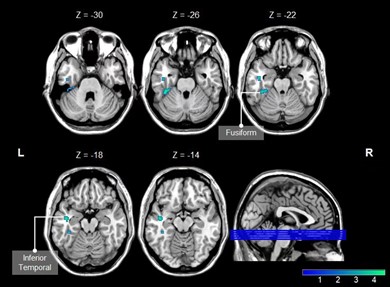

There were statistical differences in MoCA score, correct number of free recall in CVLT1 experiment, TMT-A, TMT-B and DSST between the two groups (p < 0.05) (Table 1). The CBF value was significantly reduced in brain regions of the left Fusiform (Fusiform-L) and the left Temporal Inferior (Temporal Inf – L) in the HD group compared with the HC group. The voxels, MNI coordinates, and peak intensity for these regions are shown in Table 2. Mean CBF in Fusiform -L was positively correlated with cognition (r = 0. 455, p = 0.012), and mean CBF in Temporal Inf - L was negatively correlated with TMT-A (r = -0.389, p = 0.030) (Figure 2).

Figure 1 Brain regions with lower CBF in HDs than HCs